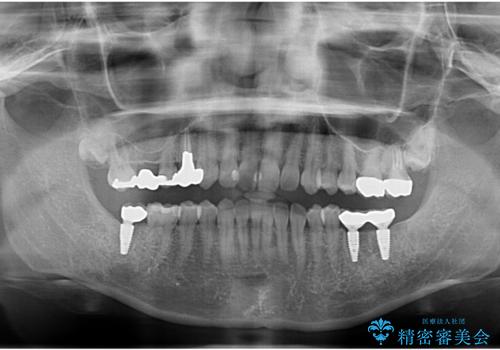

下の奥歯が虫歯になっており、痛みが生じていました。

左右の第二大臼歯は虫歯がひどく抜歯が必要な状態でした。

また、左下の第一大臼歯は歯が内側から吸収してしまう状態(外部吸収)が生じており、患者様と相談の上抜歯しました。

合計3本の奥歯を抜歯したところに、インプラント治療を行っています。

また、左上奥歯の根の治療および右下の虫歯治療も併せて行っています。